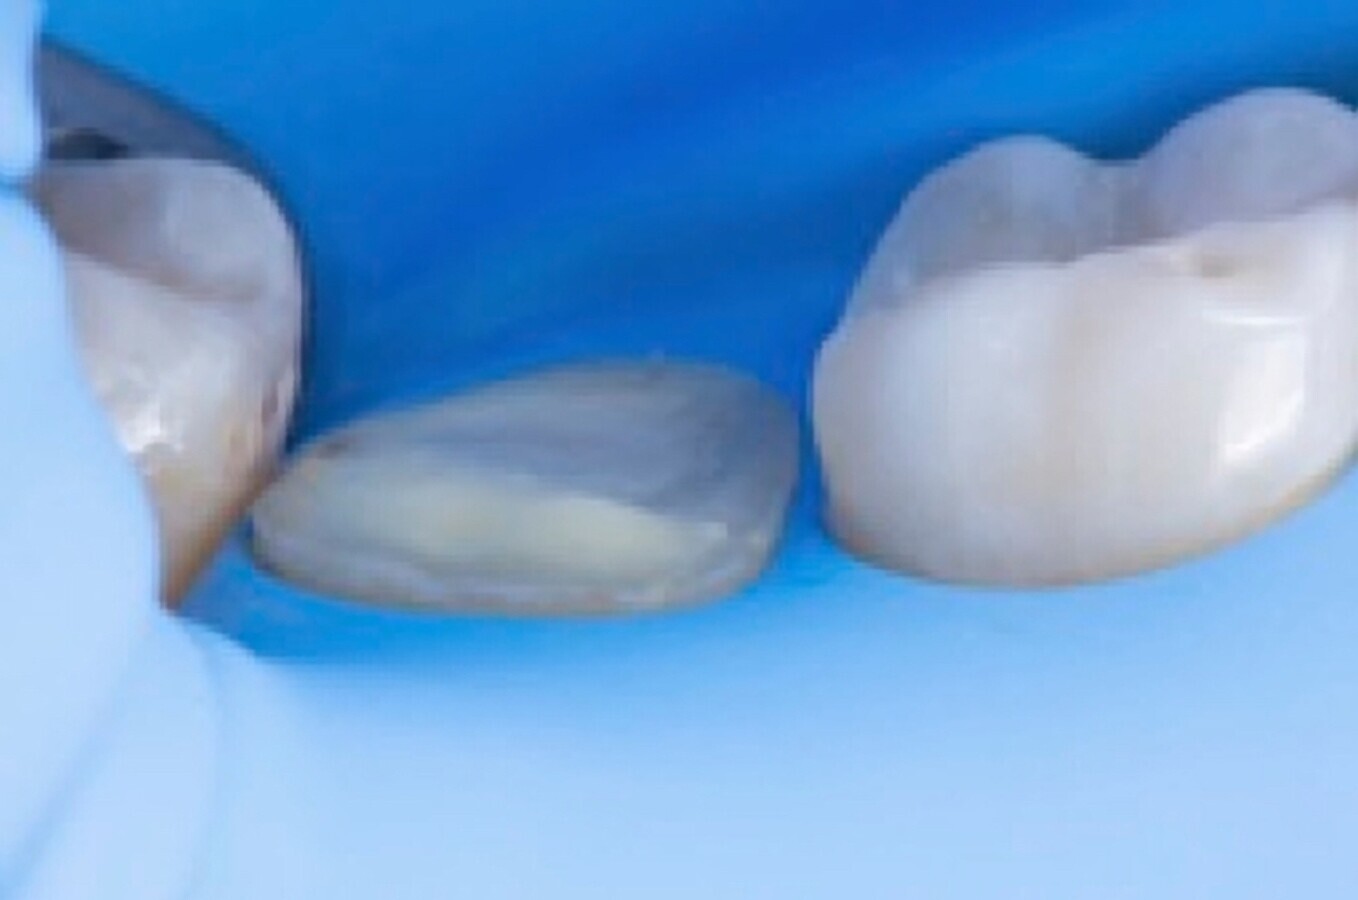

A continuación, y una vez acabado el tratamiento endodóntico y restaurador, procedemos con el tallado de la preparación de la restauración indirecta y el escaneado digital con el scanner Trios (3Shape). Se decide utilizar como material Celtra Duo (Dentsply) para la confección de un overlay para procurar un recubrimiento cuspídeo completo a este diente. Tras el fresado y confección de la incrustación, se efectúa un aislamiento absoluto con dique de goma, que va desde el 4.8 al 4.4 para su cementado (Figs. 6, 7, 8).

Fig. 6. Aislamiento absoluto del campo operatorio para la cementación del recubrimiento cuspídeo tipo overlay.

Fig. 7. Vista oclusal de la preparación del diente 4.7.

Fig. 8. Vista lateral previa a la cementación del overlay en el diente 4.7.